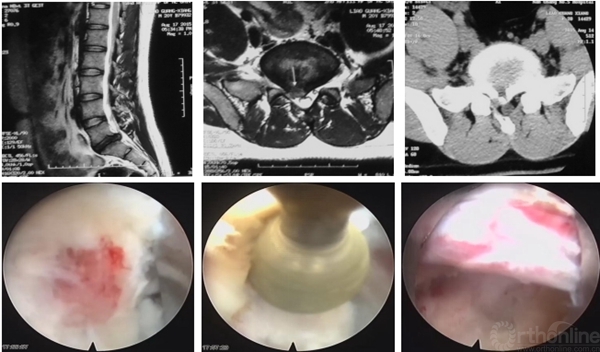

有些病例椎板间入路手术更加简单,尤其对于L5/S1脱垂病例

高度脱垂病例可选择椎板开窗入路,需准备磨钻动力系统

L5/S1钙化型突出(骺环离断症),椎板间减压更加充分彻底,需配备磨钻动力系统

4、进一步提高微创手术理念与技巧

脊柱内镜日间手术相对于非日间手术,需进一步微创化,类似于“取异物”手术,要求对于正常结构的破坏降到最低,如腰椎后纵韧带的保护就至关重要。